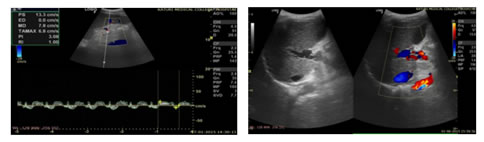

Figure 3:                                                                              Figure 4:

3

Figure 1: USG Axial image showing Dilated Portal Vein; Figure 2: USG Axial image showing Loss of Respiratory variations in Portal Vein diameter; Figure 3: Colour Doppler showing Flow reversal in Splenic vein; Figure 4: Colour Doppler Axial image: Flow reversal in SMV shown by arrow; Figure 5: USG Axial image showing dampened flow in Portal vein; Figure 6: HRUS image showing Nodular liver surface in cirrhosis

Figure 7: Spectral Doppler USG image: Showing Biphasic flow in Splenic vein; Figure 8: Gray scale and Colour Doppler USG image: Showing Cavernomatous transformation of Portal vein; Figure 9: Gray scale and Colour Doppler USG image; Figure 10: Showing Dilated Coronary vein with Hepatofugal flow; Figure 11: Gray scale and Colour Doppler USG image: Showing GEJ collaterals; Figure 12: Gray scale and Colour Doppler USG image: Showing Lienorenal collaterals; Figure 13: Gray scale and Colour Doppler USG image: Showing Recannalised Paraumbilical vein with hepatofugal flow; Figure 14: Colour Doppler USG image: Showing Absent Colour flow in Portal vein due to Thrombosis